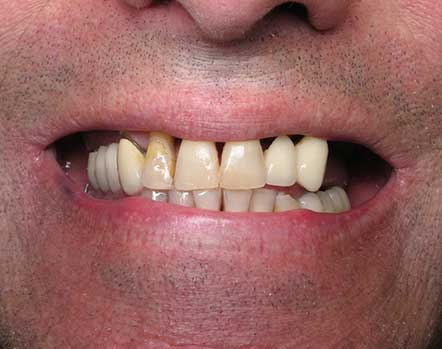

Anthony A.

This patient had only a few remaining infected teeth, but didn’t want to settle for just a denture.  Placed multiple implants and provided a secure fixed option which allowed him to not only chew better but to smile again.